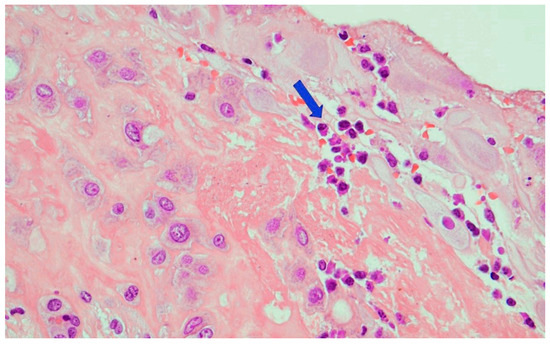

- Sheffield, J.S.; Sanchez, P.J.; Wendel, G.D., Jr.; Fong, D.W.I.; Margraf, L.R.; Zeray, F.; McIntire, D.D.; Rogers, B.B. Placental histopathology of congenital syphilis. Obstet. Gynecol. 2002, 100, 126–133. [Google Scholar] [PubMed]

- Qureshi, F.; Jacques, S.M.; Reyes, M.P. Placental histopathology in syphilis. Hum. Pathol. 1993, 24, 779–784. [Google Scholar] [CrossRef]

- Genest, D.R.; Choi-Hong, S.R.; Tate, J.E.; Qureshi, F.; Jacques, S.M.; Crum, C. Diagnosis of congenital syphilis from placental examination: Comparison of histopathology, Steiner stain, and polymerase chain reaction for Treponema pallidum DNA. Hum. Pathol. 1996, 27, 366–372. [Google Scholar] [CrossRef]

- Kittipornpechdee, N.; Hanamornroongruang, S.; Lekmak, D.; Treetipsatit, J. Fetal and Placental Pathology in Congenital Syphilis: A Comprehensive Study in Perinatal Autopsy. Fetal Pediatr. Pathol. 2018, 37, 231–242. [Google Scholar] [CrossRef] [PubMed]